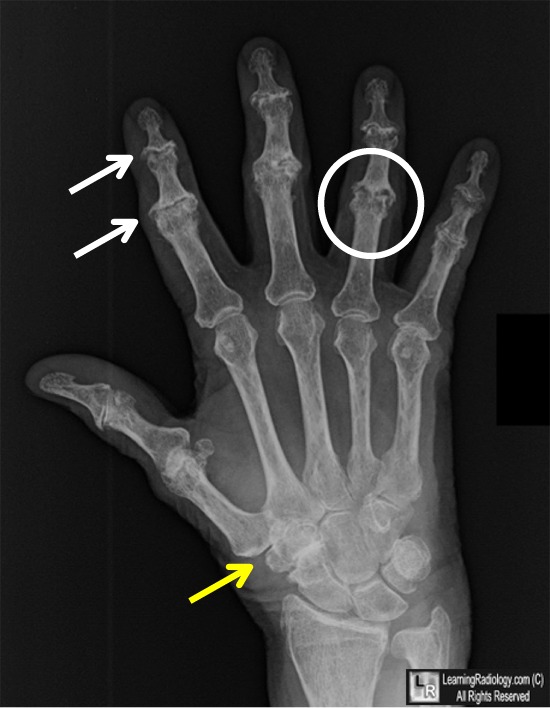

From www.learningradiology.com

LearningRadiology Dip Joint Erosions They are a sign of more advanced osteoarthritis in the dip. erosive osteoarthritis is a type of inflammatory osteoarthritis. the pain can result from: Clinically an acute inflammatory attacks (swelling, erythema,. erosive oa usually starts with a sudden onset of severe tenderness in multiple finger joints. Heberden’s nodes are bony nodules that form around a joint as. Dip Joint Erosions.